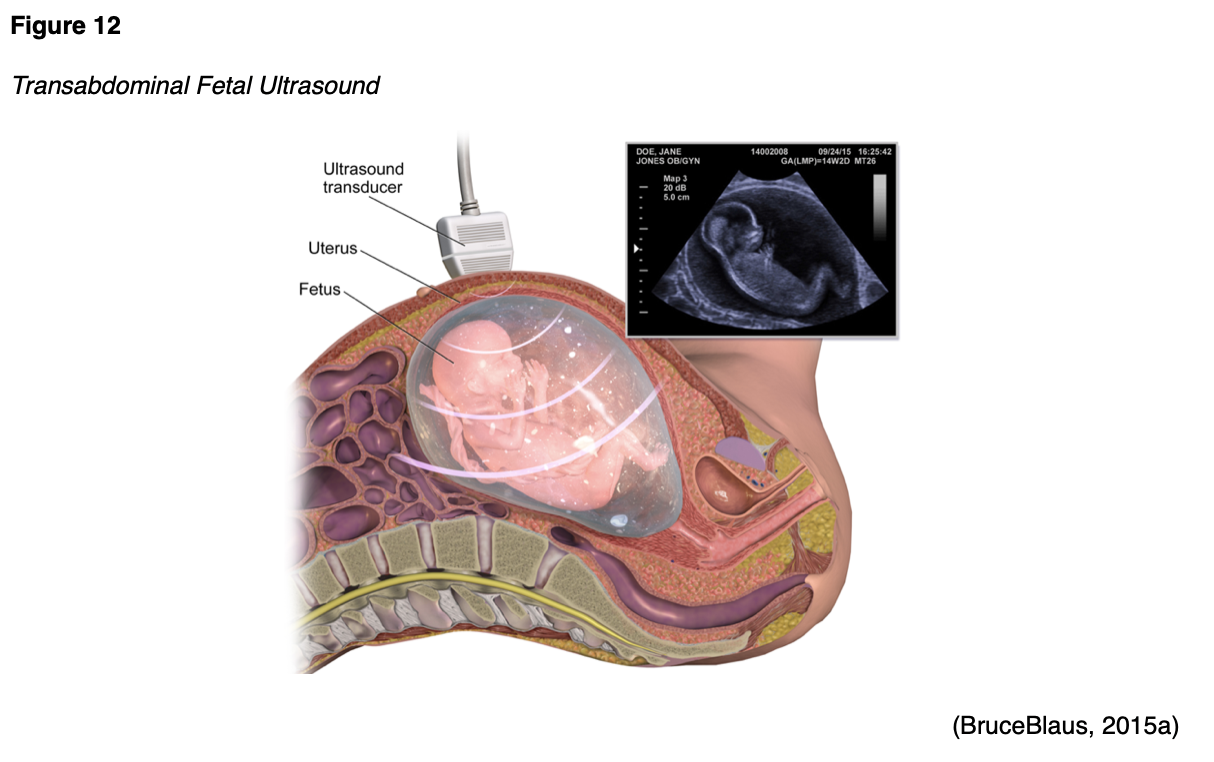

Ultrasound